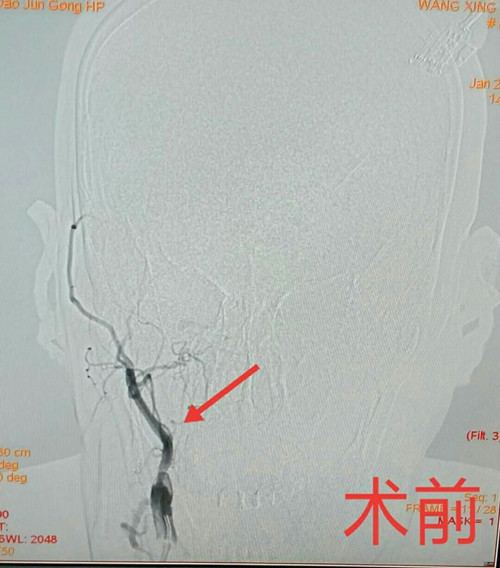

王先生,因头晕和左侧肢体无力,在军工医院神经内科住院治疗。医生给予全脑血管造影检查,结果显示右侧颈内动脉完全闭塞,右侧脑组织靠侧枝供血,侧枝代偿的血管存在重度狭窄。如果再发生闭塞,王先生发生梗塞的脑组织面积将进一步扩大,病情加重,甚至危及生命。

神经内科副主任李光雷分析患者病情:王先生脑梗塞的原因是低灌注,神经功能损伤较小,症状为阵发性头晕和左侧肢体肌力减弱,没有影响到日常生活;如果能及时开通闭塞的颈内动脉,恢复原有供血通道,不但能缓解患者的症状,还能避免再次发生梗塞的风险,提高患者生活质量。李光雷副主任与家属做了详细的病情介绍和沟通,决定于2019年1月26日14:30分,在介入中心行经皮穿刺右侧颈内动脉闭塞开通术。

术前准备完毕,在神经外科、麻醉科、急诊介入中心的全力配合下,在天坛医院高峰教授的技术指导下,经过1个半小时的精细手术,从导丝穿通、球囊扩张、血管保护,到支架置入一系列操作,患者的颈内动脉完全开通,开通长度达10厘米。术后复查头CT未见出血,血压稳定,安全度过了高灌注风险期,术后三天王先生康复出院。